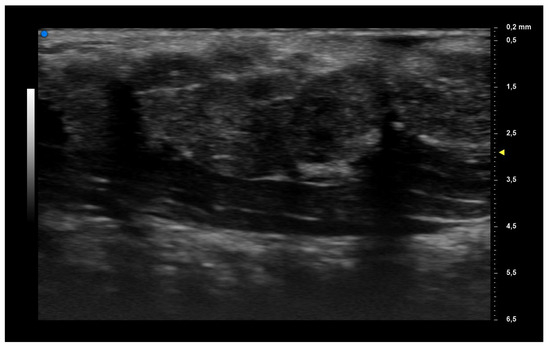

| UHFUS Characteristics | Sicca Syndrome (n = 4) | Parotitis (n = 2) | Non-Sicca, Non- Parotitis (n = 6) | Total (n = 12) |

|---|---|---|---|---|

| Grade 1 | 3 (75%) | 1 (50%) | 4 (67%) | 8 (67%) |

| Grade 2 | 0 (0%) | 1 (50%) | 1 (17%) | 2 (17%) |

| Grade 3 | 1 (25%) | 0 (0%) | 1 (17%) | 2 (17%) |

| Mild vascularization | 1 (25%) | 1 (50%) | 1 (17%) | 3 (25%) |

| Moderate vascularization | 3 (75%) | 1 (50%) | 5 (83%) | 9 (75%) |